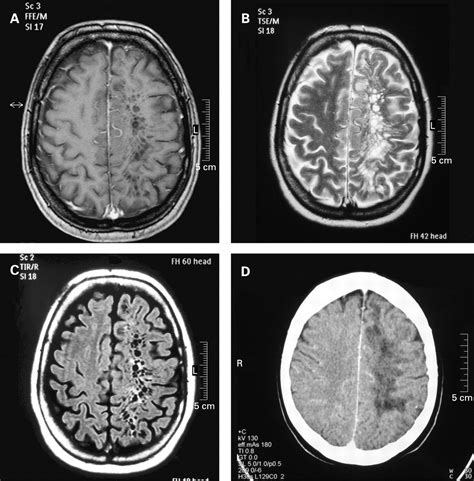

This creates a small, fluid-filled gap between the vessel wall and the brain parenchyma (the functional tissue of the brain). This gap is the perivascular space. The fluid inside these spaces is cerebrospinal fluid (CSF), which is the same clear fluid that cushions the brain and spinal cord. Because they are filled with CSF, they appear dark on T1-weighted MRI images and bright on T2-weighted images, mirroring the signal intensity of the CSF in the rest of the brain's ventricles.

One of the primary goals of a radiologist when interpreting an MRI is to differentiate a Perivascular Virchow Robin space from other, more concerning lesions, such as lacunar infarcts (small strokes) or multiple sclerosis plaques. While they might look similar to the untrained eye, there are clear diagnostic markers.

Feature Perivascular Space Lacunar Infarct

Signal Intensity Matches CSF Varies, often higher signal

Surrounding Tissue Usually no change Often shows "gliosis" (scarring)

Location Predictable anatomical paths Scattered or random

Clinical Concern Typically none (benign) Requires clinical follow-up

Advancements in MRI technology, such as 3 Tesla and 7 Tesla scanners, provide much higher resolution than older models. As our ability to see the brain in detail improves, we are "finding" more of these normal structures than we used to. This is often called the "discovery effect." What might have been invisible on a low-quality scan twenty years ago is now perfectly clear on modern equipment. Consequently, finding these spaces is not necessarily a sign that your brain is changing, but rather a sign that your imaging is highly detailed.